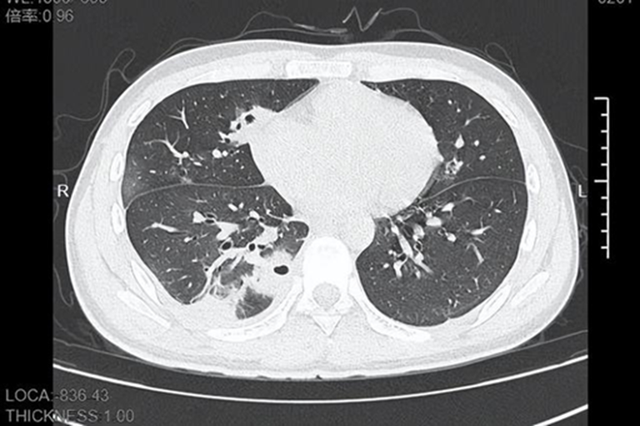

Khi tới bệnh viện, thân nhiệt Lâm đã chạm 39 độ C. CT ngực cho thấy bên trong phổi xuất hiện hơn 10 hốc rỗng, một số vùng mô phổi đã hoại tử, biểu hiện điển hình của áp-xe phổi do vi khuẩn từ đường máu.